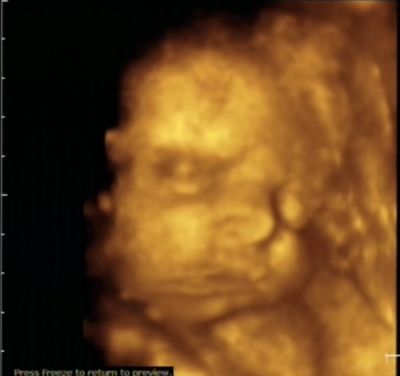

Mijn profiel en minineusje die ik graag tegen de BM wand aan druk als ik niet mijn voetje er tussen heb :P (Ow ja, de kleine kriebelt me dus niet met de handjes zoals ik dacht maar t zijn dus de voetjes die de kleine bij, naast, boven en onder t hoofdje houd).

Boos kijken:

Lachen:

Enne ja, Geen facepalm op de traditionele manier maareuh... Mat de voet dus :p Gewoon omdat het kan XD